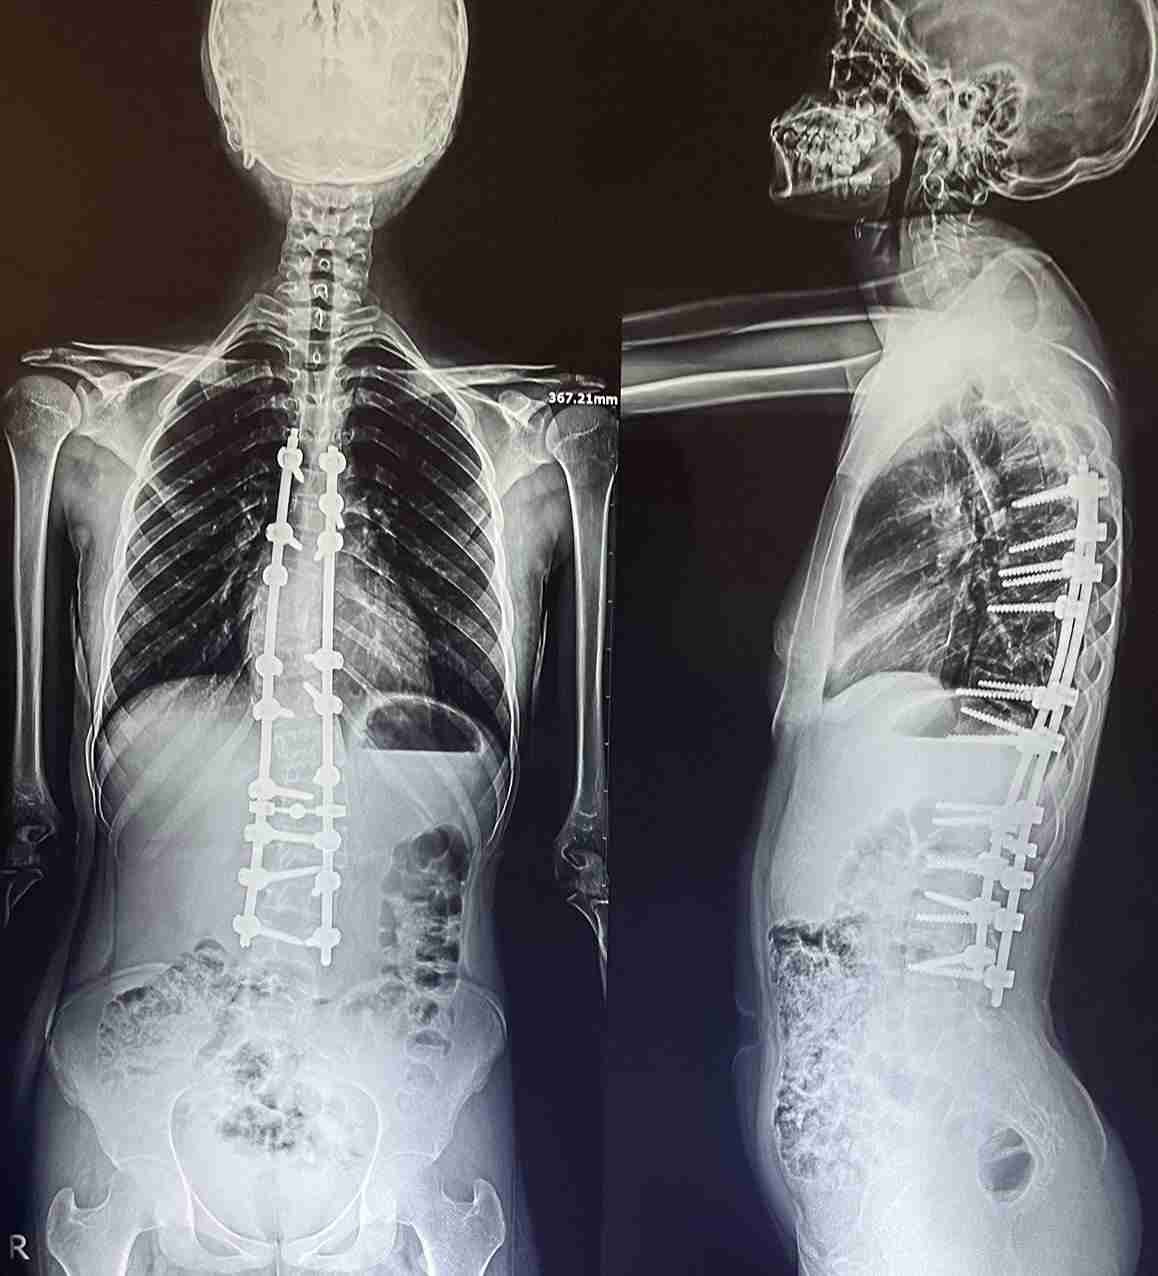

اعوجاج مزدوج بالفقرات الصدرية و القطنية

double curvature of the thoracic and lumbar vertebrae

An advanced corrective surgery was performed to treat double curvature in thoracic and lumbar vertebrae. This condition involves abnormal curvatures in both the chest and lower back areas of the spine, affecting posture, movement, and causing chronic pain.

• Correcting double curvatures in thoracic and lumbar vertebrae

• Restoring balance and alignment to the spine

• Improving posture and external appearance

• Relieving chronic back pain

• Enhancing breathing and lung function